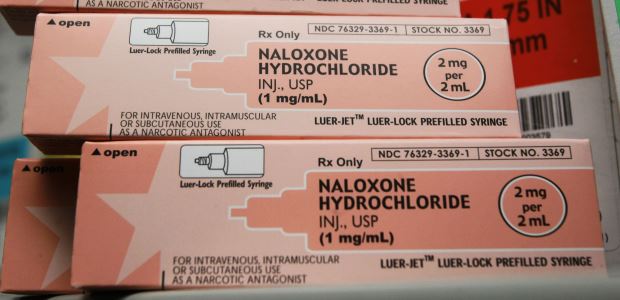

According to the governor's office, opioid overdose deaths are now the leading cause of accidental deaths in nearly every part of Washington state, surpassing motor vehicle deaths and firearm-related deaths, and 718 people died from opioid overdoses in Washington last year.